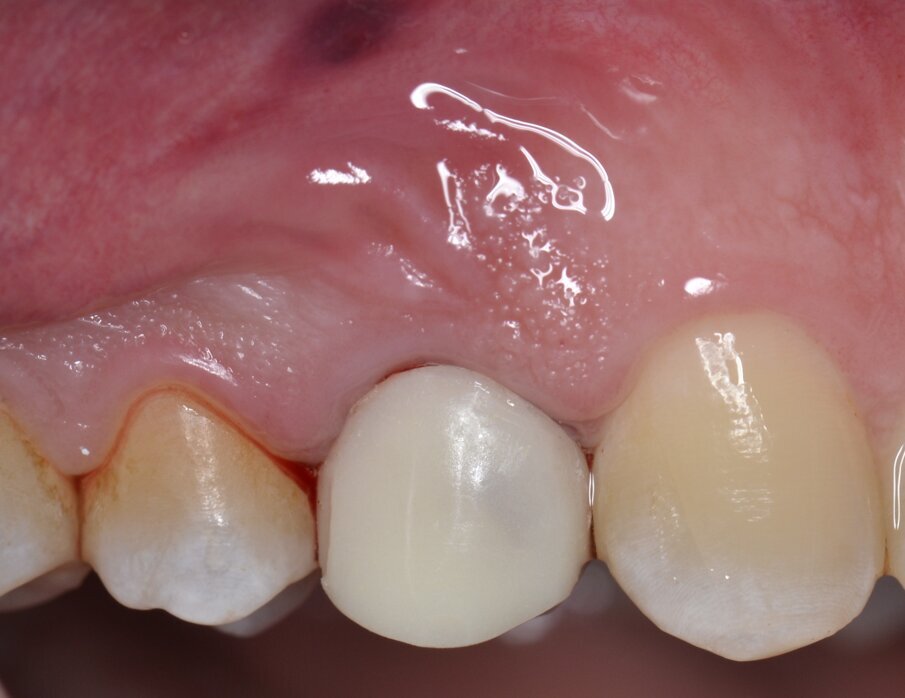

All’esame obiettivo viene si evidenzia una frattura verticale a carico dell’elemento in questione (Figg. 1, 2) che pone indicazione assoluta all’estrazione dentaria; per evitare di aggravare l’inevitabile contrazione della cresta ossea alveolare, si decide di eseguire l’estrazione dell’elemento fratturato senza sollevare alcun lembo. Viene effettuato un esame radiografico endorale allo scopo di visualizzare la morfologia della radice dentaria e i suoi rapporti con le strutture viciniori. (Fig. 3)

Fig. 1 - Elemento 1.4 fratturato (visione occlusale).

Fig. 2 - Elemento 1.4 fratturato (visione buccale).